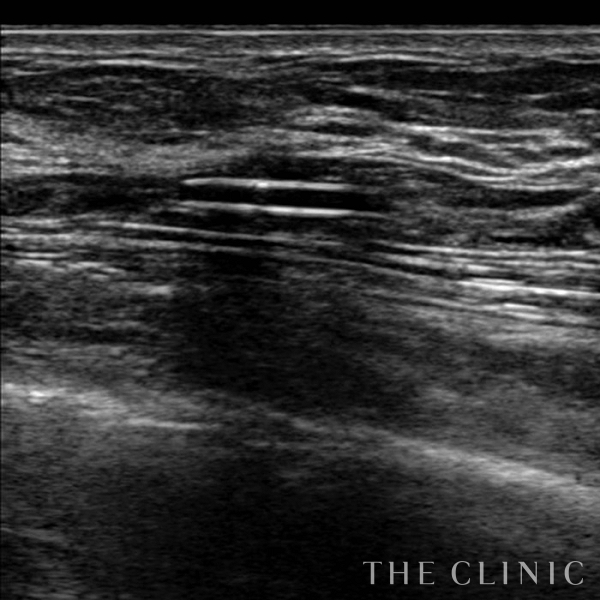

コンデンスリッチ豊胸を行うために、前もってアクアフィリングの除去を行いました。エコーで確認するとかなり厚い被膜が形成されています。

アクアフィリングは生理食塩水で溶解されるとのことで、エコー下に生理食塩水を注入しましたが、なかなか溶解できず、ヒアルロニダーゼも追加してなんとか溶解除去することができました。右側は炎症があった為か、汚く濁った状態でした。